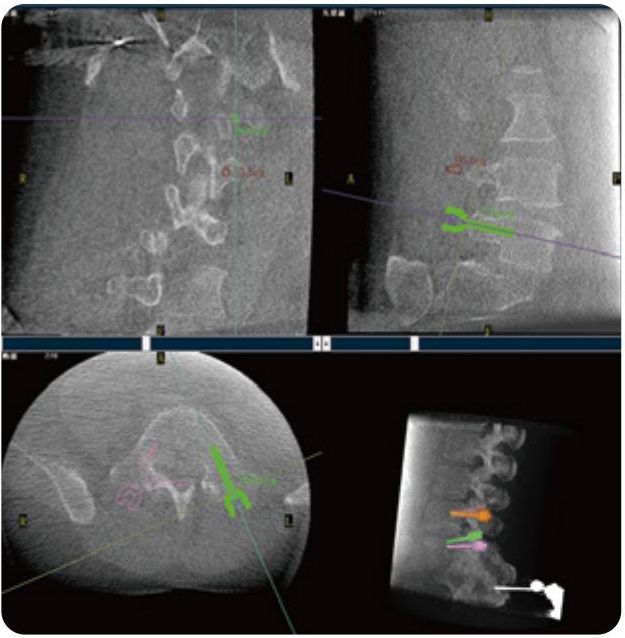

PL300B可應(yīng)用于多節(jié)段脊柱外科手術(shù),輔助醫(yī)生定位病灶部位,為脊柱外科手術(shù)(經(jīng)皮椎體成形術(shù)、椎弓根螺釘內(nèi)固定術(shù)等術(shù)式)提供術(shù)前手術(shù)流程規(guī)劃、入釘位置、角度可視化引導(dǎo),模擬仿真入釘輔助。

PL300B搭配普愛醫(yī)療自主研發(fā)生產(chǎn)的平板3D C形臂,借助一體化自適應(yīng)配準(zhǔn)( 軌跡配準(zhǔn))技術(shù),通過追蹤C(jī)形臂三維采集軌跡,自動完成圖像坐標(biāo)建立和系統(tǒng)坐標(biāo)配準(zhǔn)。配準(zhǔn)精度更高,操作步驟少,系統(tǒng)運(yùn)作效率高。